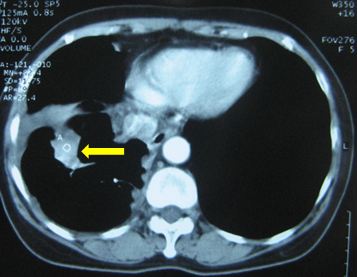

Chụp PET/CT:

Hình 4: Hình ảnh PET/CT có khối u thùy dưới phổi phải 2,6 × 2,8 cm, Max SUV= 5,32